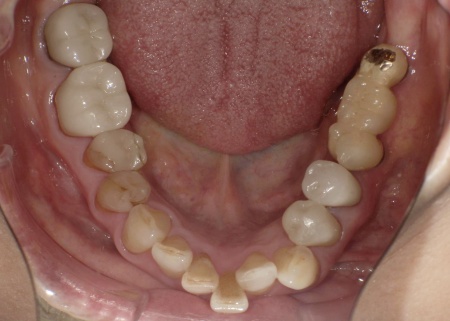

70代女性 歯根が折れた歯を抜いて金属バネを使用しない部分入れ歯で補った症例

拝見したところ、左上の歯(第2小臼歯)が欠損しており、この部分を補うために、両隣の歯を土台として橋を渡すように連結した被せ物「ブリッジ」が装着されていました。

レントゲン撮影をして詳しく検査した結果、ブリッジを支えている左上の歯(第1小臼歯)は、歯根が割れていることが判明しました。

今回は審美性を考慮して、金属のバネではなく樹脂の留め具で固定する部分入れ歯「ノンクラスプデンチャー」を提案し、同意いただきました。

ノンクラスプデンチャーの留め具は歯茎に近い色をしているため、目立ちにくいのが特徴です。

まず、歯根が折れた左上の第1小臼歯を抜きます。

3ヶ月間の経過観察後、傷が治癒したことが確認できたため、ノンクラスプデンチャーを作製するための型取りを行いました。

また、噛み合わせの記録を取ったり、周囲の歯に馴染む色調の人工歯を選んだりなど、患者様によりぴったりと合う入れ歯に仕上げています。

約3週間後、完成した入れ歯を装着し、使用感や見た目に問題がないことを確認して、治療を終了しました。

第1小臼歯に歯根破折を認めました。